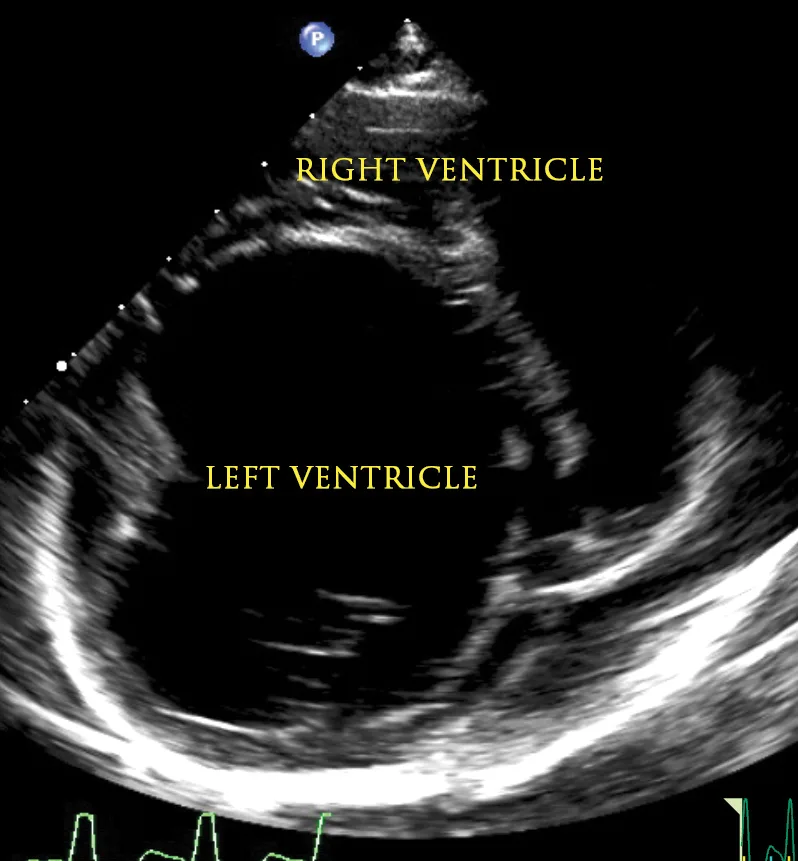

An echocardiogram and thoracic radiographs were obtained. The echocardiogram revealed decreased left ventricular (LV) wall thickness, severe dilation of the LV chamber (ie, eccentric hypertrophy), and severely reduced LV systolic function. Severe left atrial enlargement with a moderate degree of centrally directed left atrioventricular valve regurgitation (suspected functional) was observed. The left atrioventricular valve leaflets appeared normal in thickness with poor coaptation due to annular stretch. In addition, there was mild dilation of the right atrium and ventricle with a mild degree of right atrioventricular valve regurgitation. Results of echocardiography were consistent with dilated cardiomyopathy (DCM; Figures 1-4).2,3

Figure 1

2D echocardiographic image of the left ventricle from the right parasternal short axis view. There is decreased thickness of the LV walls and severe dilation of the LV cavity consistent with DCM.